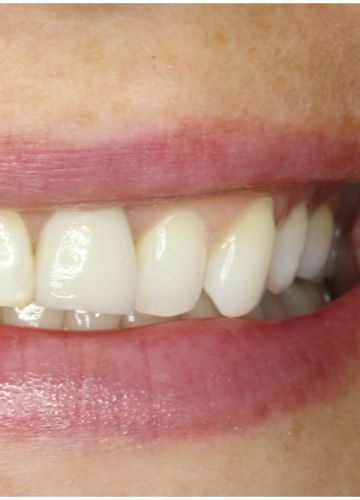

• Pēc 5 mēnešiem tika izgatavots slāņots cirkonijkeramikas kronis

• Tika  nomainītas vecās plombas priekšzobu rajonā